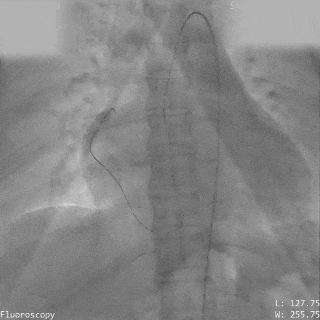

左盘展开

保留导丝技术

展开封堵器左盘

超声下可见左盘面贴靠主动脉侧

右盘展开

右盘面展开后

前推钢缆使其成型

超声下可见双盘面骑跨

释放前瓣上造影

分流明显减少